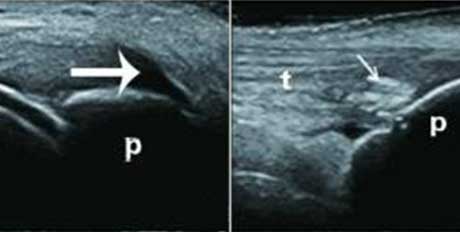

回声伴声影

膝关节髌上囊扩张积液,可见团状强回声,并伴声影

高回声团

关节横纵扫描图像,尿酸盐沉积形成略高回声团块-痛风石